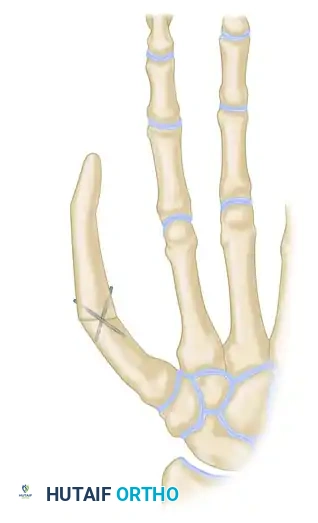

Bone Graft Harvest and Fixation

A corticocancellous bone graft is harvested from the ipsilateral iliac crest. It must be meticulously sculpted to match the approximate length and thickness of the normal contralateral thumb.

* Sizing: The tip of the reconstructed thumb, when adducted, should reach within approximately 1 cm of the index finger proximal interphalangeal (PIP) joint.

- Excise any scar tissue from the thumb bone stump and freshen the bone end to bleeding cortical bone.

- Create a recess (step-cut or peg-in-hole) in the base of the proximal phalanx or the thumb metacarpal.

- Insert the sculpted iliac crest bone graft into the recess.

Fix the bone graft rigidly using crossed Kirschner wires (K-wires), intraosseous wiring, or small fragment plates and screws.

Biomechanical Alignment: For amputations at or proximal to the MCP joint, the iliac bone block must be fixed in approximately 30 degrees of flexion and 45 degrees of internal pronation. This precise positioning is critical to allow functional opposition of the reconstructed thumb to the fingers.